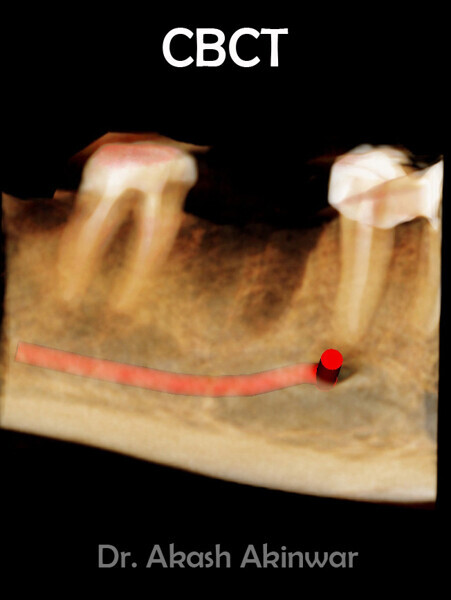

Flapless Single Implant Placement with Screw Retained PFM Prosthesis: Dr Akash Akinwar